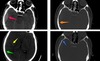

What imaging is used in this picture? [1]

dopamine transporter (DaT) - DaT scan